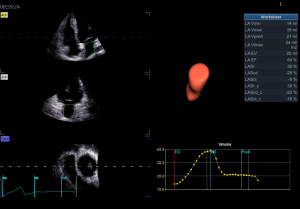

Image acquisition and data analysis of RT-3D Auto LAQ

RT-3D Auto LAQ image acquisition operation guidelines: (I) use the 4Vc matrix probe was to obtain two-dimensional images at the standard four-chamber heart section, and adjust the sector depth and gain to make the left atrium clearly visible in all the apex views; (II) Breath-hold at end-expiration; acquire 4–6 cardiac-cycle four-dimensional (4D) full-volume loops; (III) transfer to EchoPAC; select the best loop, open 4D Auto LAQ; (IV) at end-systole, place the sampling point at the mid-mitral annulus in each apical plane; align axes; (V) activate the “review” interface to check whether the LA endocardium curve automatically outlined by the system is consistent with the real endocardium. If there is any deviation, manually drag and drop the sampling line to make it coincide with the endocardium while excluding the pulmonary vein inlet and LA auricle area, then click “result” for LA volumes and strain, as shown in Figures 1-4. The LA volume parameters are divided by the body surface area (BSA) of each case to obtain the corresponding volume indices. Further calculations are performed to determine the left atrial total emptying fraction (LATEF) = (LAVmax-LAVmin)/LAVmax; left atrial passive emptying fraction (LAPEF) = (LAVmax-LAVpreA)/LAVmax; left atrial active emptying fraction (LAAEF) = (LAVpreA-LAVmin)/LAVpreA; and left atrial expansion index (LAEI) = (LAVmax-LAVmin)/LAVmin. The LA function parameters include the left atrial storage period strain (LASr), the left atrial conduit period strain (LAScd), the left atrial systolic period strain (LASct), and the corresponding left atrial storage period circumferential strain (LASr-c), left atrial ductile period circumferential strain (LAScd-c), and left atrial systolic period circumferential strain (LASct-c) (16). Among them, LAEI, LASr, and LASr-c represent the storage function of the left atrium; LAPEF, LAScd, and LAScd-c represent the function of the LA duct; and LAAEF, LASct, and LASct-c represent the active contraction pump function of the left atrium. All parameters were averaged twice.